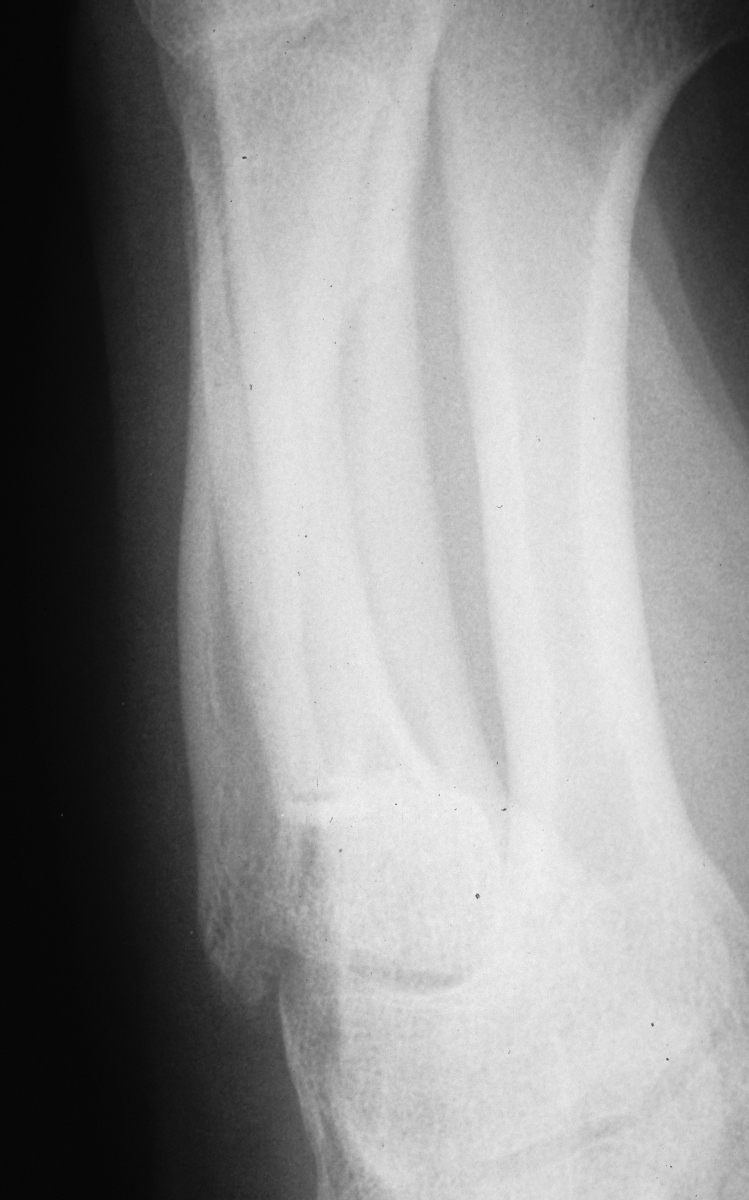

Displacement of femoral neck fracture will disrupt the blood supply and cause an intracapsular hematoma (effect is controversial).

Carol lin, md & brad merk, md. There is at least a theoretically increased risk if reduction is determined to be adequate, then a guide pin may be placed through a percutaneous incision. With special reference to percutaneous knowles. Twenty three patients had other medical conditions. A femoral neck fracture most often results from a recent fall on the affected hip. Garden 1 fractures collapse less frequently than garden 2 fractures, but both have high rates of fracture collapse when treated to union with in situ percutaneous pin fixation. Femoral neck fractures close to the hip joint are easy to recognise. It is a fracture that is commonly found in older individuals who are suffering from osteoporosis and athletes. Displacement of femoral neck fracture will disrupt the blood supply and cause an intracapsular hematoma (effect is controversial). The femoral neck (femur neck or neck of the femur) is a flattened pyramidal process of bone, connecting the femoral head with the femoral shaft, and forming with the latter a wide angle opening medialward. There were 36 garden grade iii and 26 grade iv fractures. Treatment may consist of repair or replacement. Femoral neck fracture is a type of hip fracture common in elderly, osteoporotic women. Carol lin, md & brad merk, md. They generally lead to immediate immobility. The wire is driven into the femoral head. Femoral neck fractures are a subset of proximal femoral fractures.